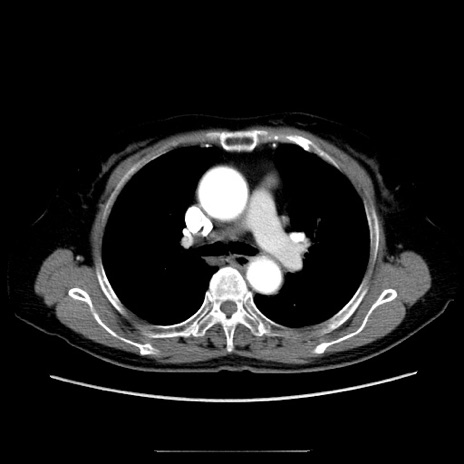

症例5(横断像)

【症例】70歳代女性

【主訴】お腹が張る

【現病歴】1週間くらい前から腹部膨満の自覚あり。昨日夜から増悪したため、本日救急外来受診。

【身体所見】意識清明、BT 36.5℃、BP 165/106mmHg、HR 80bpm、SpO2 98%、腹部:膨満、軟、自発痛・圧痛なし、触診にて不快感あり、腸蠕動音:減弱

【データ】WBC 12600、CRP 1.04